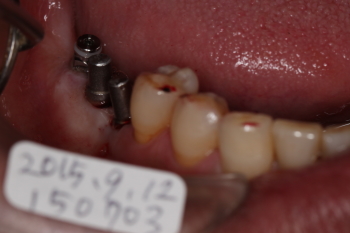

| @:一番奥のインプラントがエミネオです。 それより2本は、ねじ込み式インプラント(4.25mm、Mサイズです。 歯軸を考慮して植立します。従って、すぐにでも最終補綴が印象出来るような角度で植立します。 左上の3本は、先月(08月)に植立。 現在、TEKの状態で、噛んでもらっています。予後良好。 |

| ねじ込み式インプラントに、テック(仮歯)を作り、その日のうちにその場所で食事を出来るよう作ります。 エミネオの部分は、骨と結合するまで数カ月待ちます。歯肉がかぶらないように、エミネオはこの状態で放置します。 |

| テック(仮歯)を装着した状態です。 ミラーを使って、舌側から見た写真です。 上記の写真の裏側です。 |